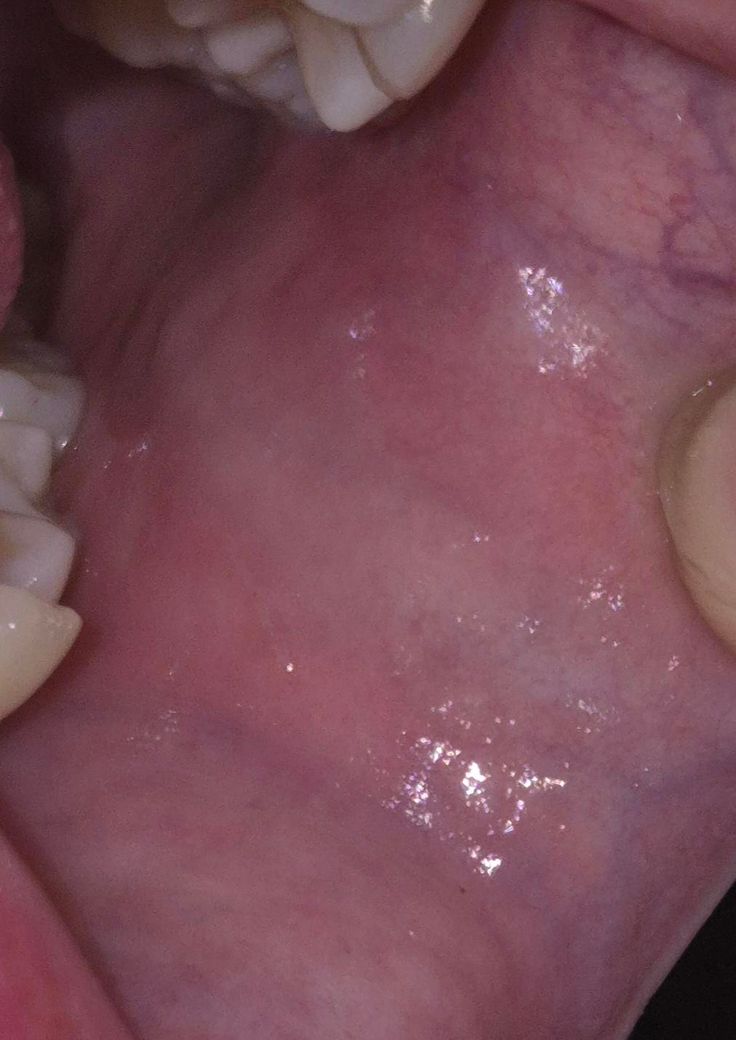

볼 안쪽에 얇고 짧은 선같은게 있는데 뭔가요?

혀로 만져 봤을 때 엄청 얇고 짧은 선 같은 게 만져져요. 혀로 느껴지는거면 튀어나왔다는건데 걱정돼서요.

제가 트랙션?장치를 끼고 자는데 그것때문일까요?

볼살이 치아에 눌리면서 생긴 자국입니다. 큰 문제가 잇는건 아니니 걱정하지 않으셔도 될것같습니다.

장치가 자극이 되어 그럴 수도 있고, 볼을 자주 씹어서 생긴 압흔일 수도 있습니다 특별히 병적인 건 아닐 것 같습니다